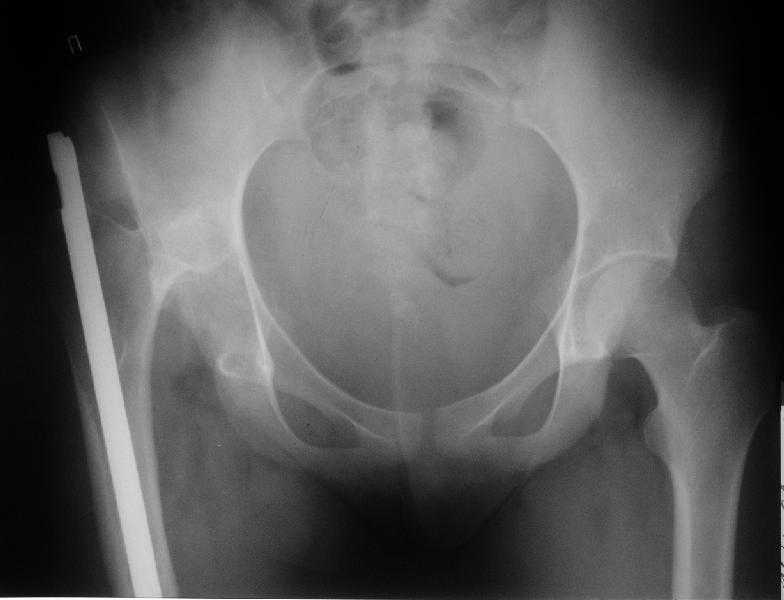

Больная 18 лет. Травма 12.08.2007. Лечилась в одном из городов Свердловской области.

15.08.2007 в ЦРБ сделан открытый остеосинтез правого бедра интрамедуллярным стержнем, после чего была наложена гипсовая кокситная повязка и пациентка лечилась амбулаторно в течение 1,5 месяцев. На контрольном Rn исследовании в марте 2008 диагностирован подвздошный вывих правого бедра. <br><br>

Поступила к нам в отделение. В отделении первым этапом был наложен аппарат внешней фиксации для низведения  бедра. 30.09.08 интрамедуллярный стержень удален. Вторым этапом планируется эндопротезирование. В настоящее время у больной имеется контрактура коленного сустава, с амплитудой движений в пределах 30 градусов., и выраженный остеопороз вертлужной впадины и проксимального отдела бедра. Больныя пердвигается самостоятельно с опорой на здоровую ногу и костыли. <br><br>

Какие проблемы при эндопротезиовании в этих условиях ожидать, и как с ними бороться? Еще и диафиз сросся не очень крепко, опасаемся, как бы не сломать. Очень выражен местный остеопороз, может быть, сделать все-таки цементный протез? Хотя 18 лет всего. Спасибо.